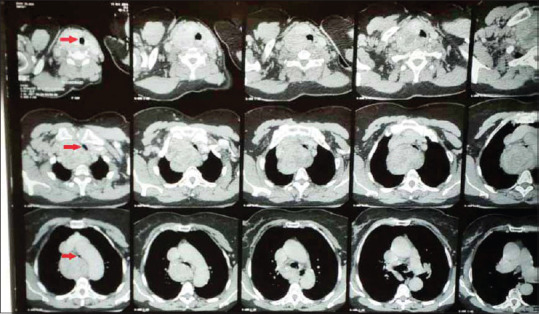

对于由于胸骨后甲状腺肿压迫气管而预期插管困难的患者,存在多种选择。在这种微妙的情况下,选择何种技术来保护气道通常取决于气道阻塞的位置和程度、可用的资源/设施以及麻醉师的经验和偏好。我们报告的情况下,68岁的妇女严重气道阻塞从胸骨后甲状腺肿来全甲状腺切除术。气道管理从清醒光纤插管开始,进行气管切开术,最后在早期技术失败后使用刚性支气管镜获得足够的通气。

A number of options exist for patients with anticipated difficult intubation on account of a retrosternal goiter compressing on the trachea. The chosen technique(s) to secure the airway in this delicate situation often depends on the location and degree of airway obstruction, available resources/facilities, and an anesthetist's experience and preferences. We report the case of a 68-year-old woman with severe airway obstruction from a retrosternal goiter coming for total thyroidectomy. Airway management started with an awake fiber-optic intubation, proceeded to a tracheostomy and finally to use of a rigid bronchoscope following failure of the earlier techniques to achieve adequate ventilation.